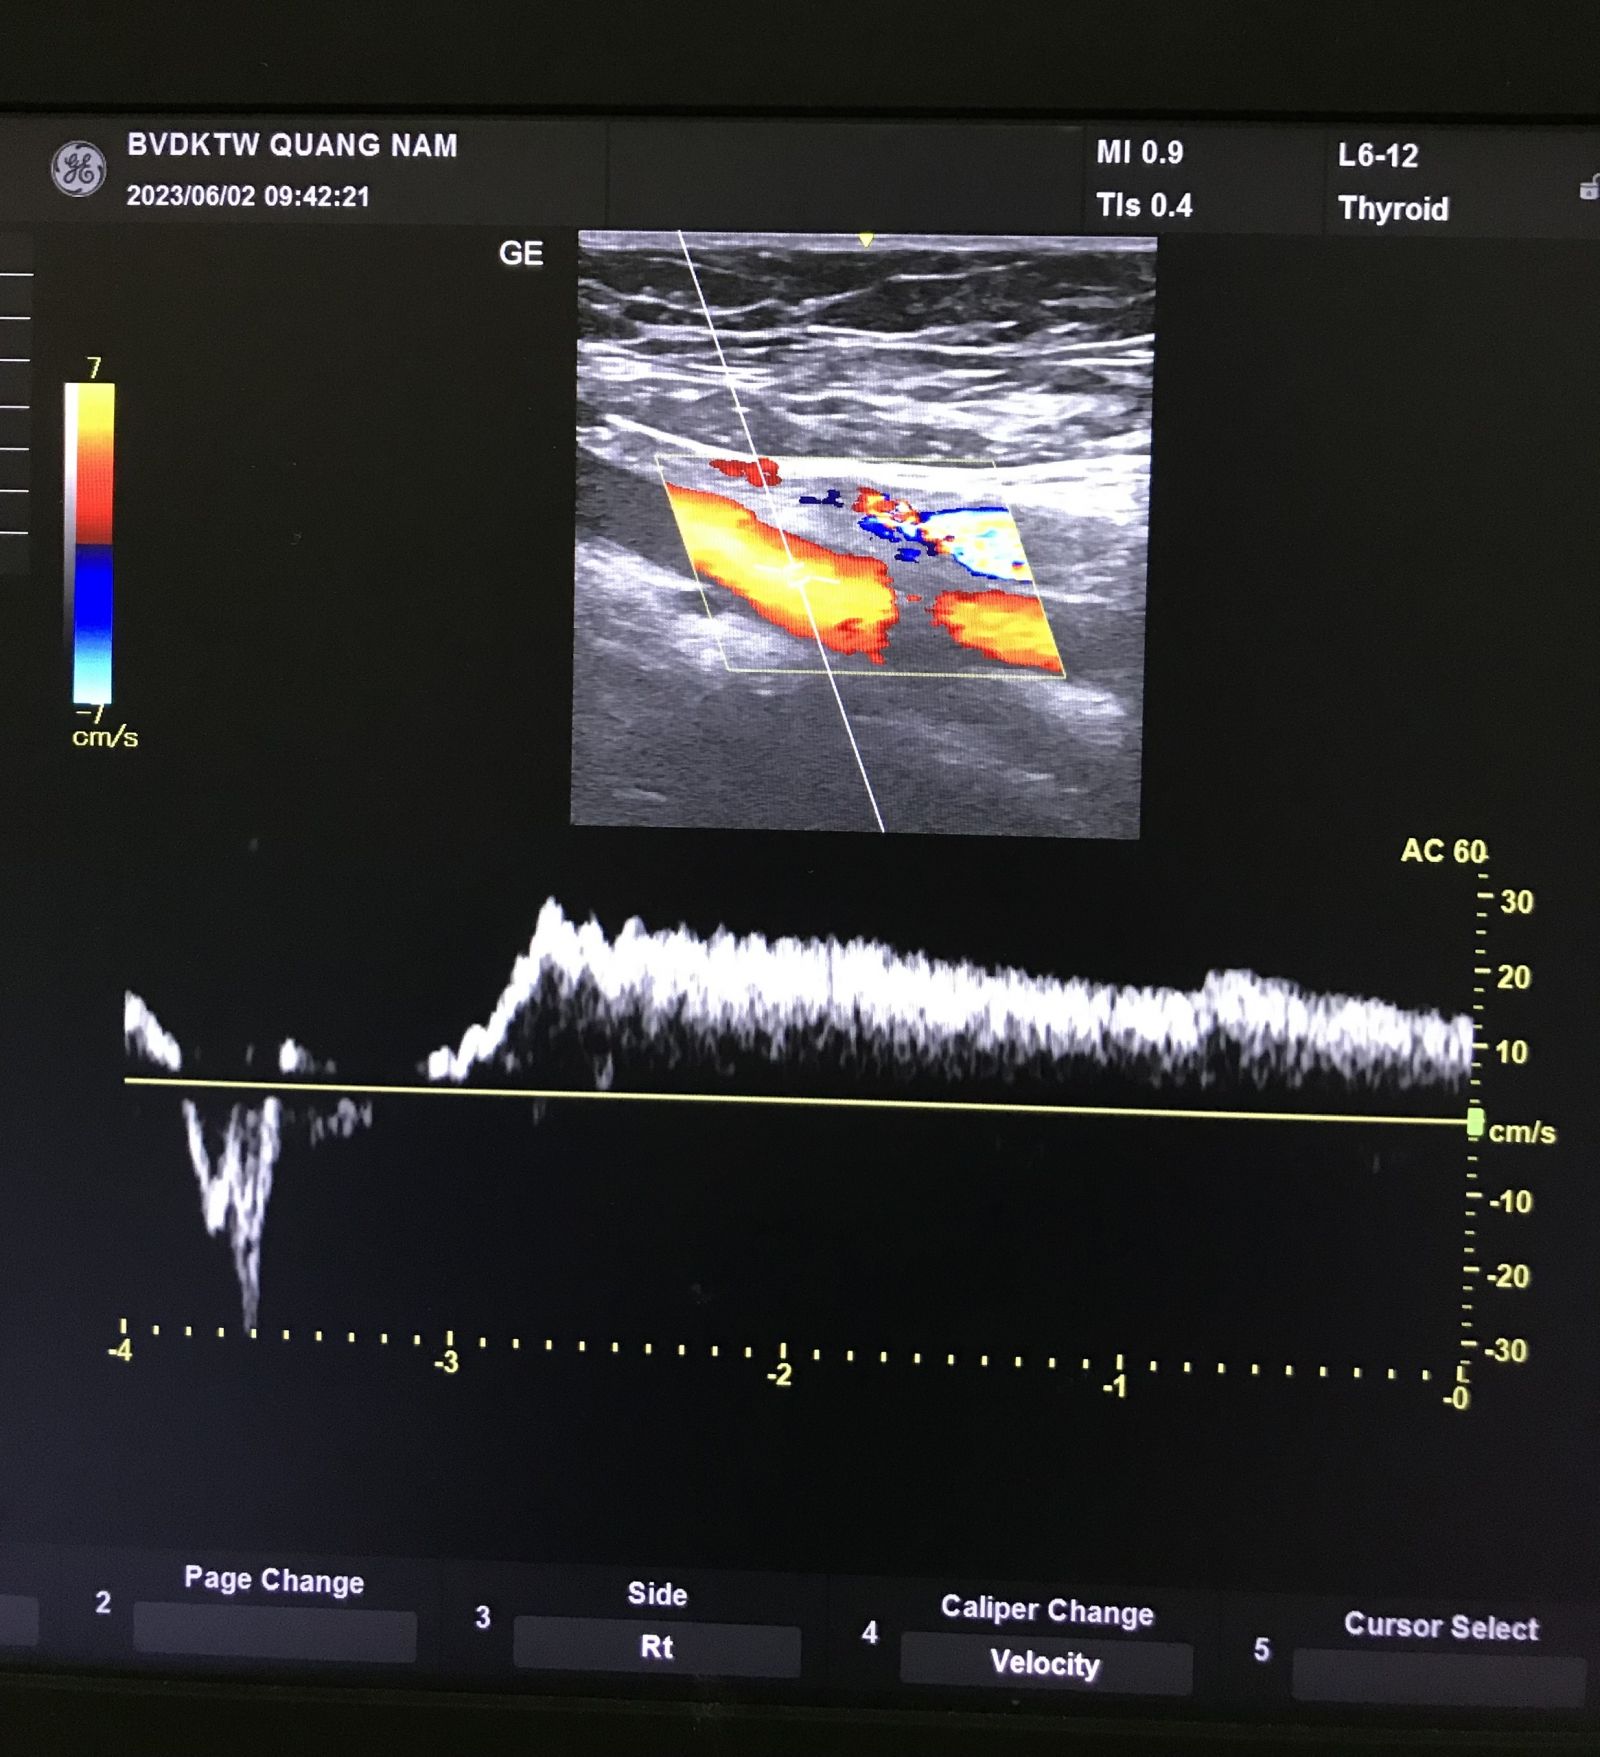

Tại Khoa Nội Tim mạch, Bệnh viện Đa khoa Trung ương Quảng Nam là đơn vị tiên phong trong tầm soát, chẩn đoán và điều trị bệnh lý suy giãn tĩnh mạch chi dưới theo mô hình đa chuyên khoa, sử dụng các thiết bị hiện đại: Siêu âm Doppler đánh giá huyết động học ở tư thế đứng, hệ thống CT scan và hệ thống cộng hưởng từ (MRI) chụp mạch máu chuyên sâu.

Siêu âm Doppler giúp phát hiện dòng trào ngược trong tĩnh mạch.